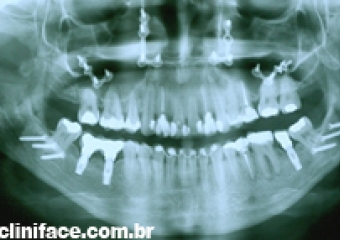

Raio x panorâmico final - Clínica Cliniface

Raio x panorâmico final